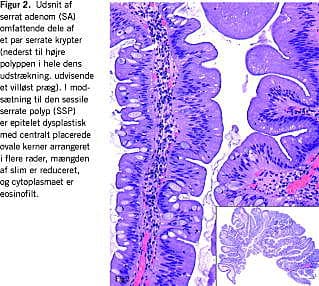

Betegnelsen serrat adenom (SA) blev introduceret i 1990 [2] af Longacre & Fenoglio , der fremhævede, at den neoplastiske mucosa kan have en serrat profil, en observation, der dog allerede var antydet få år tidligere [25]. Denne konfiguration præger således både THP og SA, men er oftest yderligere accentueret og kompleks ved SA med involvering af dybe dele af krypterne, der tillige kan være dilaterede, forgrenede og horisontalt orienterede. Til forskel fra THP ses neoplastisk kernemorfologi, og epitelets cytoplasma kan fremtræde mere eosinofilt (Figur 2 ). Fravær af endokrine celler hører med til billedet. Nogle forfattere fremhæver en inkomplet mucinøs uddifferentiering [16], andre rapporterer derimod om høj slimproduktion [27]. Det morfologiske spektrum er bredt, varierende fra polypper, der er klart neoplastiske, til polypper, der er vanskelige at differentiere fra THP [14]. Selv morfologisk lighed med normal tyndtarmsslimhinde har været omtalt [4]. Grænsen dels over for det konventionelle adenom, især det tubulovilløse adenom, dels, i tilfælde af beskeden dysplasi, over for THP, kan således være vanskelig at definere. Der har endog været sat spørgsmål ved det betimelige i at differentiere mellem neoplastisk og nonneoplastisk serrat polyp [28]. Diagnosen SA accepteres af nogle grupper, såfremt mindst 20% af det undersøgte polypområde udviser ovennævnte morfologi [16], mens andre har sat grænsen ved 50% [29]. Af disse grunde varierer den rapporterede forekomst af SA. Blandt kolorektale adenomer angives SA at udgøre fra 1,3 til 6% [29, 30]. Der foreligger flere molekylærbiologiske studier af SA [9, 15, 17]. Mutation af protooncogenet BRAF samt DNA-hypermetylering, medførende mikrosatellit-instabilitet, ses ofte. Mutation af protoonkogenet K-ras er rapporteret at forekomme med vekslende incidens [15, 17]. I modsætning til forholdene ved konventionelt adenom er APC og beta-catenin-mutationer derimod usædvanlige [31].